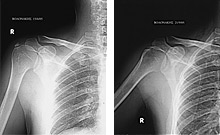

Παραθέτουμε τις ακτινογραφίες.

Η εναπόθεση ασβεστίου φαίνεται καθαρά στις ακτινογραφίες αριστερά, ενώ αυτές δεξιά έχουν ληφθεί μετά την εφαρμογή της θεραπείας όπου το ασβέστωμα έχει εξαλειφθεί.